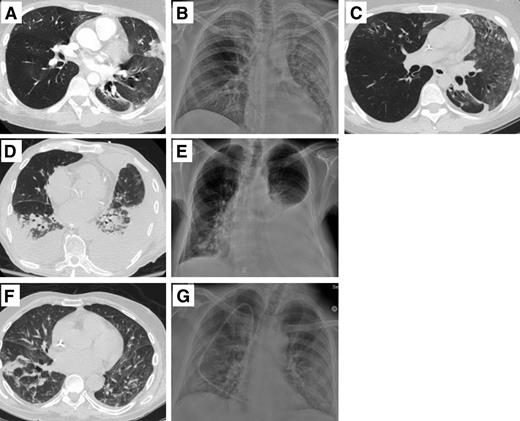

Six of 7 patients had abnormalities on chest radiograph including patchy or diffuse consolidations (Table 1). Three patients had chest computed tomography (CT) abnormalities that were consistent with lower tract disease, although 1 patient had evidence of underlying lung disease (Figure 2). Seven of these patients could be classified as lymphopenic (absolute lymphocyte count <1 × 109 cells/L) at the onset of their respiratory illness; 5 of these had an absolute lymphocyte count <0.5 × 109 cells/L. The only patient without lymphopenia at diagnosis (case 6) developed lymphopenia by day +3 after EV-D68 was diagnosed. Three patients also developed neutropenia during the course of their respiratory illness, presumably related to the recent receipt of chemotherapy.

Selected radiographic images from patients with presumptive EV-D68 infection. (A) Case 2, day −3 CT: ground glass opacities and nodule airspace opacities throughout, and consolidation in lingula and L lower lobe. (B) Case 2, day +3 chest radiograph (CXR): diffuse L lung disease and patchy R lung disease; possible bilateral pleural effusion. (C) Case 2, day +18 CT: worsening ground-glass L upper lobe, and patchy ground-glass R right upper and middle lobes. (D) Case 3, day −1 CT: patchy consolidation R lower lobe, and nodules in both lower lobes; mild interlobular septal thickening. (E) Case 3, day +4 CXR: bilateral basilar consolidation. (F) Case 7, day +1 CXR: increased left pleural effusion with underlying atelectasis; increased right lower lobe consolidation. (G) Case 7, day +4 CT: interval increase R pleural effusion; large L pleural effusion. New patchy consolidation R middle lobe; bilateral lower lobe consolidation.